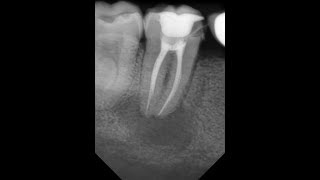

Первый этап включает предварительное обследование и подготовку зуба для лечения, также может потребоваться рентгеновский снимок.

Затем стоматолог проводит процедуру удаления поврежденной пульпы и очистки корневых каналов.

В завершении лечения, после проведения корневой обработки, стоматолог заполняет и запечатывает каналы, чтобы предотвратить повторное воспаление.

Мед. обработка корневых каналов, пломбирование гуттаперчей и гидроокисью кальция. Лечение.